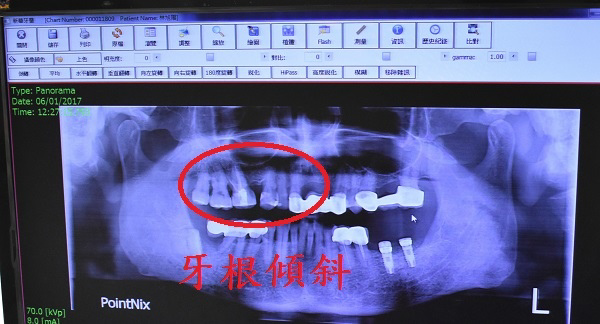

但也因為這次牙痛才發現我左上方缺了多年的臼齒

造成兩側牙齒已逐漸慢慢向空缺處傾斜

若沒有補起來日後兩側牙根都會網缺口處倒下

就像下面這張圖所描述